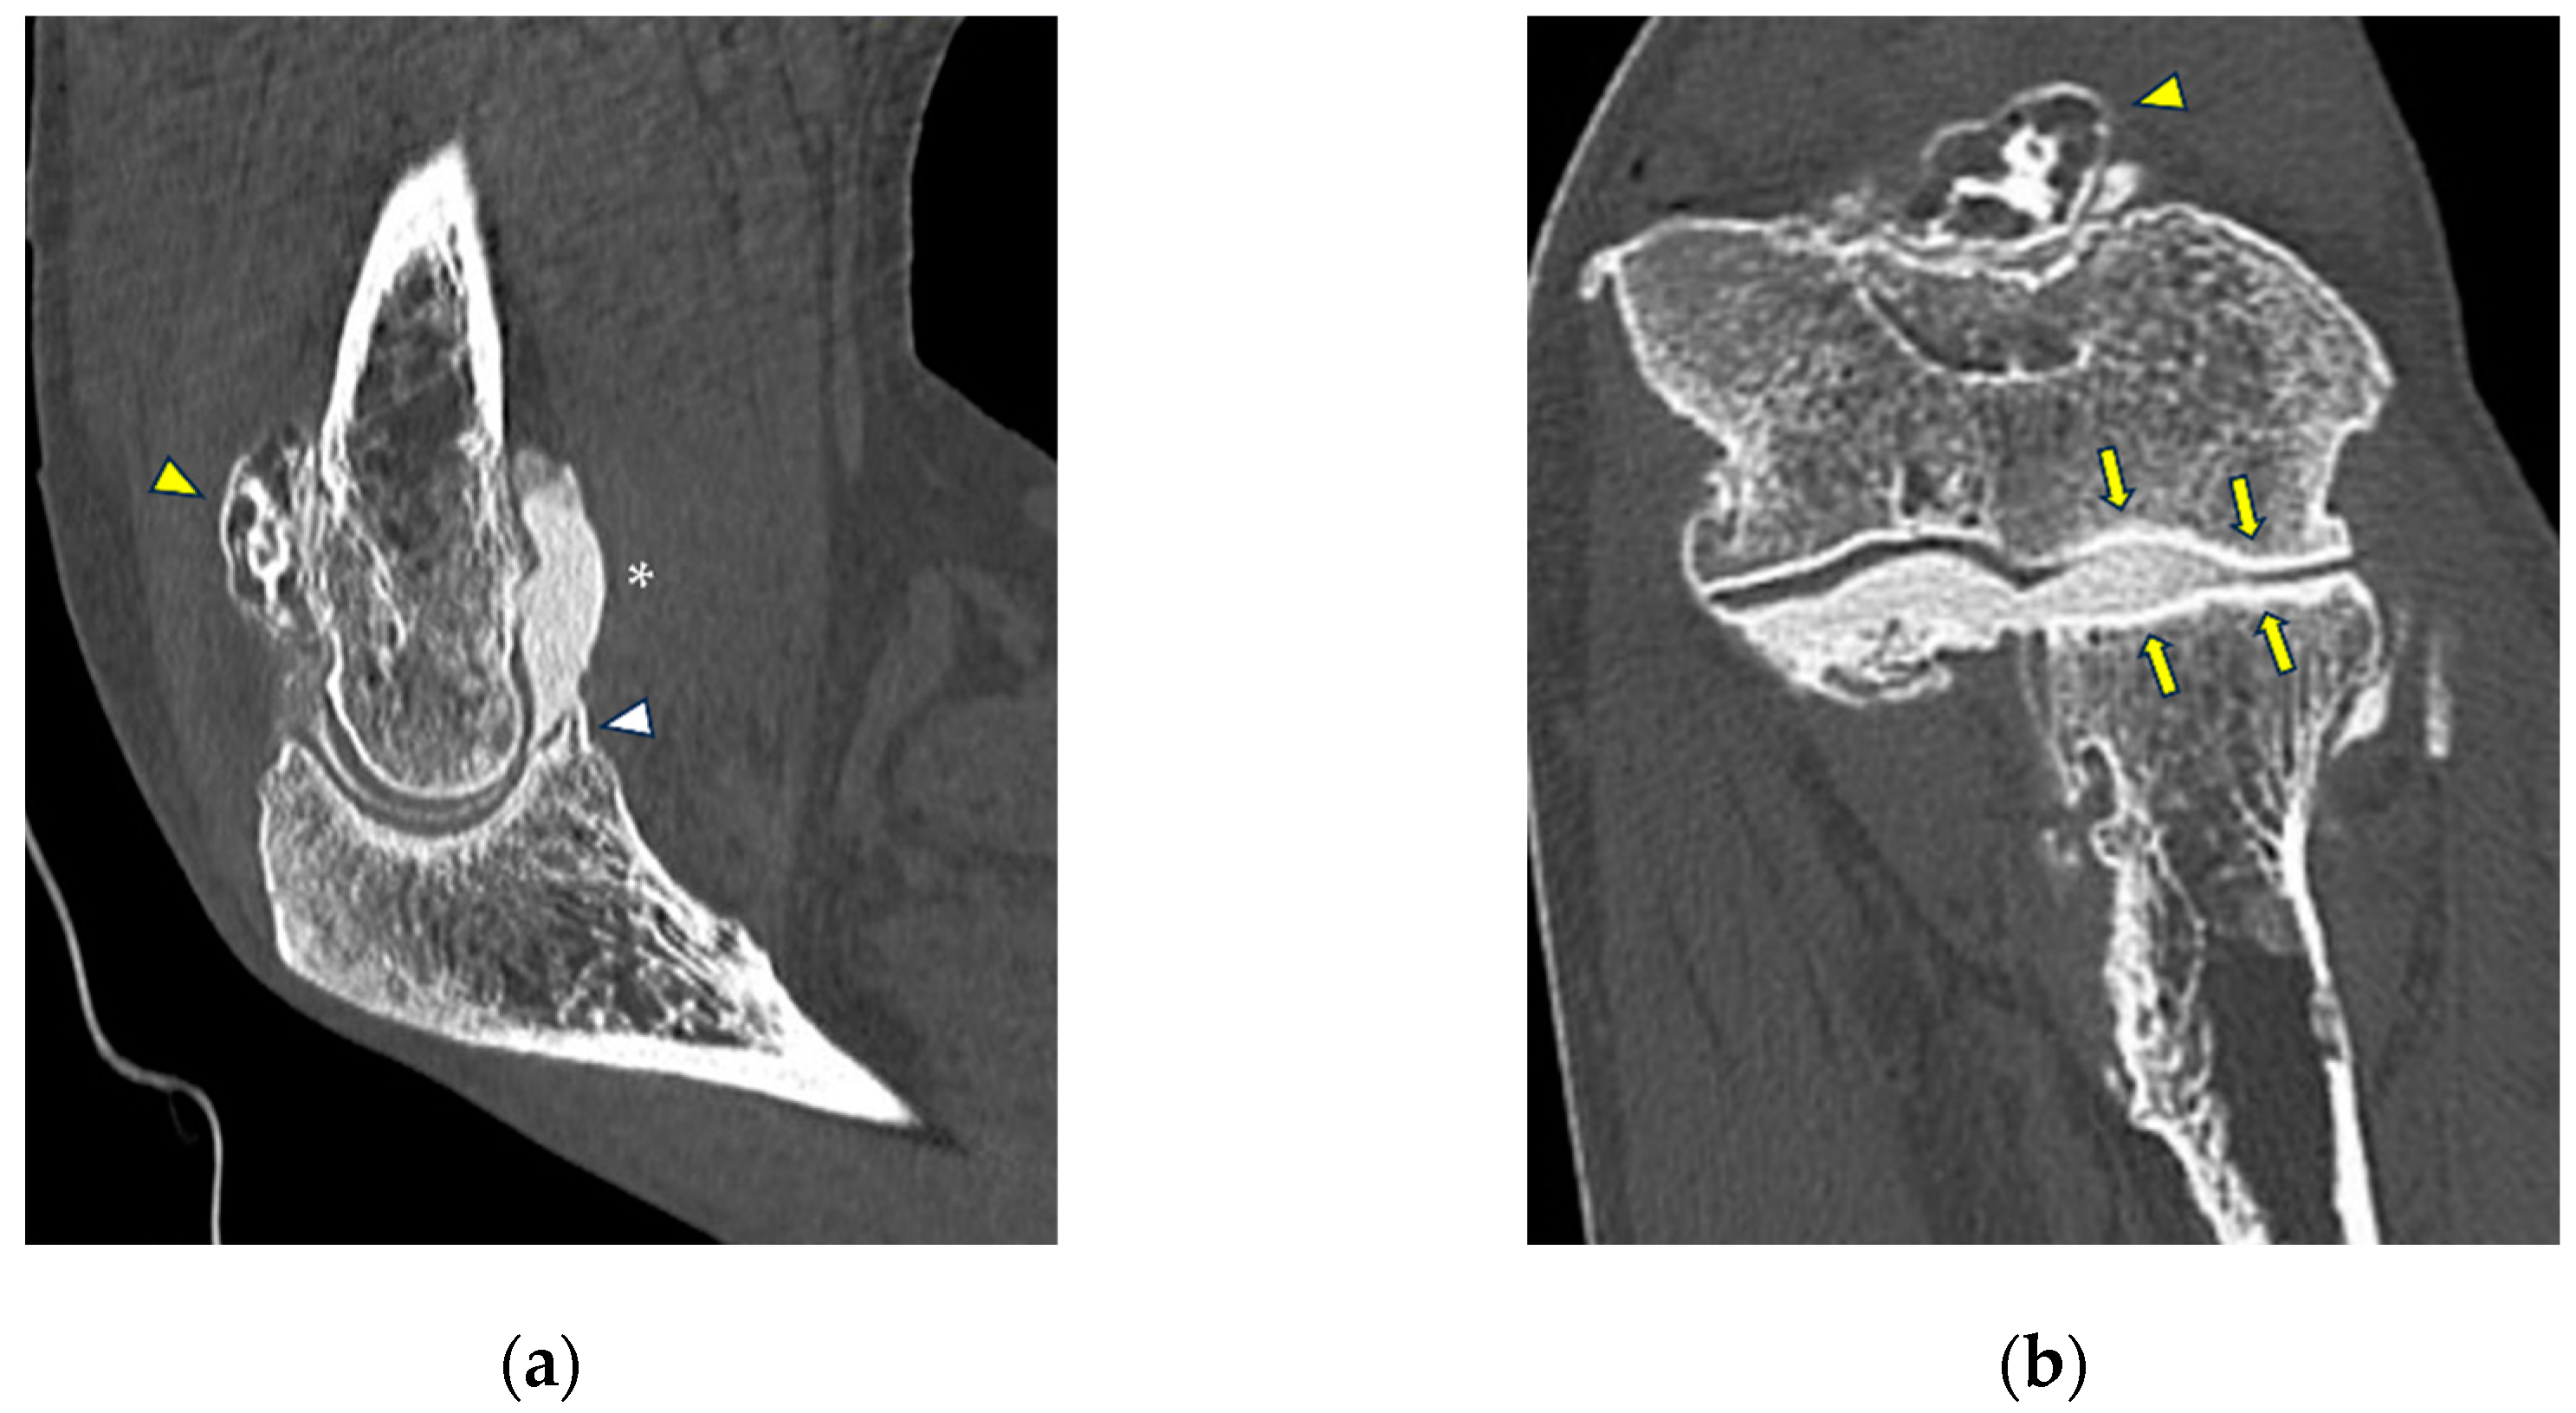

MCL injuries are typically caused by overuse [44]. Chronic injuries to the MCL may lead to medial elbow instability [50], which most often occurs in athletes who participate in overhead throwing sports such as baseball, javelin throwing, volleyball, golf, polo, and football. As stated previously, the main types of ligaments lesions that can be visualized at CT arthrography are represented by thickening or full-thickness or partial tears, which, however, in this setting are usually accompanied by other chronic local changes, such as the formation of osteophytes, presence of loose bodies or synovial thickening (Figure 6) [51]. The medial compartment may also present with posteromedial elbow impingement, which may in turn be associated with elbow instability due to MCL insufficiency [52]. Posteromedial elbow impingement is considered as a feature of valgus extension overload syndrome, presenting with pain, swelling, chondral injuries located into the posterior trochlea and the anterior and medial olecranon, postero-medial osteophytes, and loose bodies [52]. Imaging is essential for treatment decision-making, given that MCL tears would need surgical reconstruction after removal of osteophytes and loose bodies [53].

Figure 6.

CT-arthrography of a professional motocross rider with chronic elbow pain due to repeated microtraumatism. (a,b) Axial and sagittal images show pathological widening of the postero-lateral recess (yellow arrows); (b,c) sagittal and coronal images show articular asymmetry of the humero-radial joint (asterisks), diffuse cartilage fraying and a full-thickness chondral defect (grade IV) of the posterior aspect of the radial head dish (yellow arrowhead).

Figure 7.

CT arthrography of a patient with overuse-related lateral elbow pain. (a) Sagittal image shows pathological widening of the radio-humeral and radio-annular recesses (white arrowheads) due to ligamentous laxity—in particular, the annular ligament (white arrow) is displaced distally to the proximal half of the radial head side, which also shows anterior cartilage thinning and synovial thickening (asterisk); (b) the corresponding coronal reformat may aid in precise localization of the proximal extremity of the annular ligament, which can be visualized as a hypodense band anterior to the radial head (white arrows); in this instance, it shows marked distal displacement.

Figure 8.

CT arthrography of a patient with lateral epicondylitis subjected to multiple corticosteroid injections. (a,b) Coronal and axial images show extravasation of intra-articular contrast into lateral periarticular soft tissues through a large full-thickness tear of both the radial collateral ligament and the proximal common extensor tendon (white arrowheads). Diffuse thinning of radial head dish cartilage is also displayed (white arrows); (c) sagittal image also shows distal displacement of the annular ligament (yellow arrowhead) and cartilage fraying of the radial head side (yellow arrow).